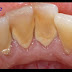

| Tình trạng cổ răng bị mòn |